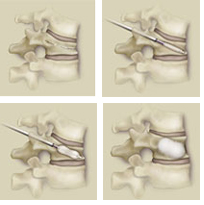

Cifoplastia

Técnica quirúrgica de refuerzo vertebral mínimamente invasiva que se realiza de manera ambulatoria o en estancia hospitalaria de un día. Consiste en crear una cavidad y restablecer la altura del cuerpo vertebral. |